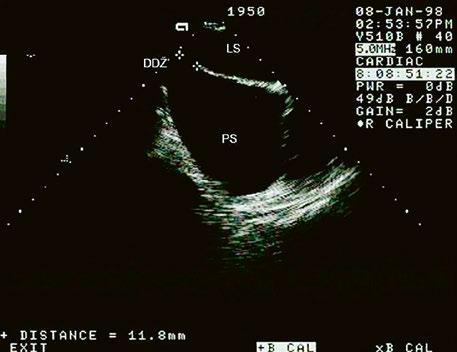

Obr. 45.1 Defekt septa síní typu II v TEE

AO – aorta, DDŽ – ústí dolní duté žíly do pravé síně, defekt septa síní je označen křížky, má předozadní průměr 22 mm, zasahuje blízko zadní stěny levé síně, LS – levá síň, PS – pravá síň